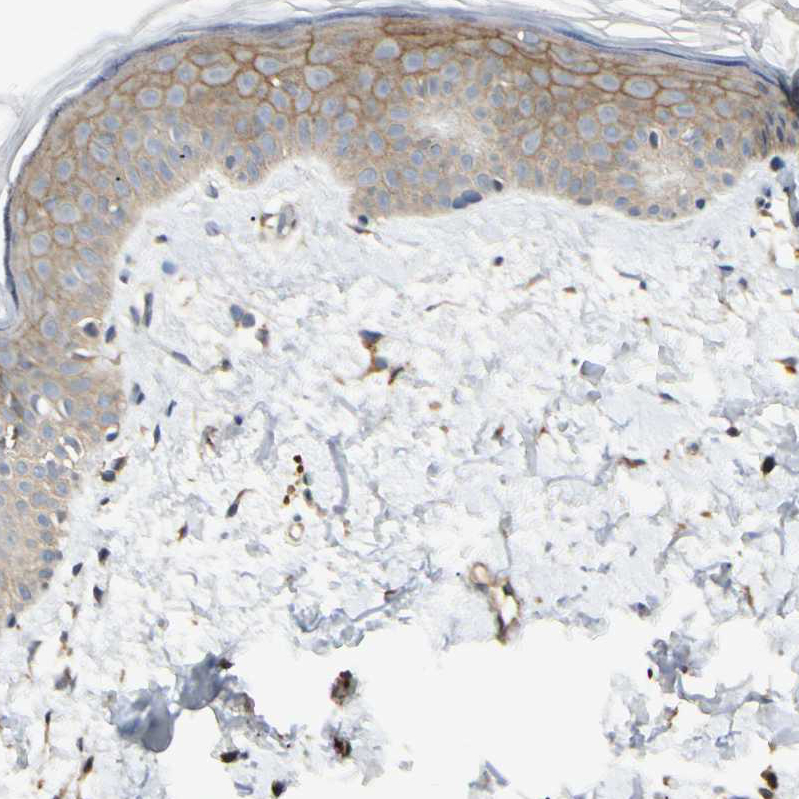

Immunohistochemical staining of human placenta shows strong cytoplasmic positivity in trophoblastic cells.